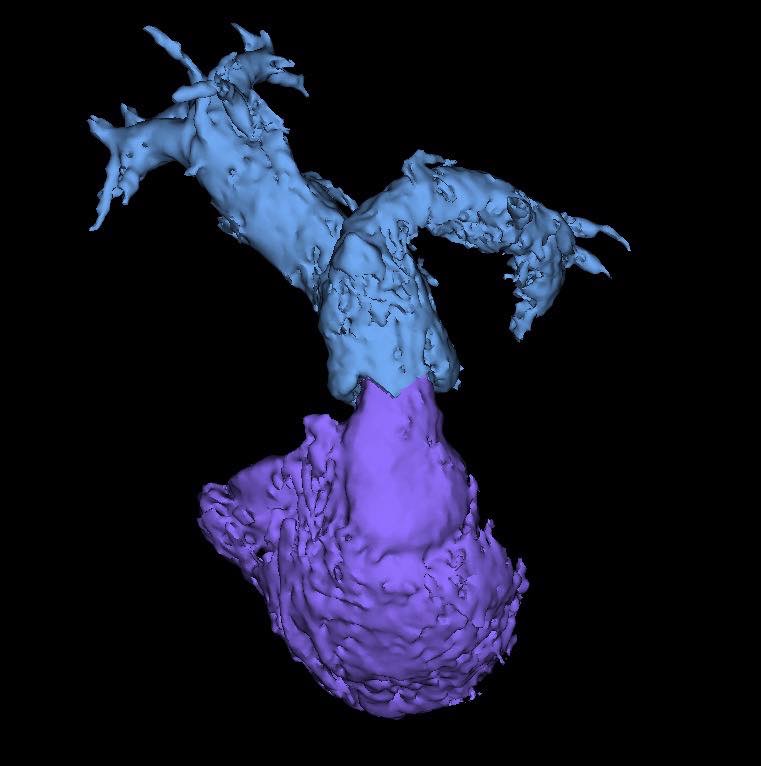

คณะแพทยศาสตร์ มช. สร้างความสำเร็จทางการแพทย์ ด้วยการรักษาโรคลิ้นหัวใจพัลโมนิกรั่ว (Pulmonary valve regurgitation) ผ่านสายสวน ในผู้ป่วยหญิงไทย อายุ 22 ปี ที่มีประวัติผ่าตัดรักษาภาวะ Tetralogy of Fallot มาก่อน และมีอาการของลิ้นพัลโมนิกรั่วรุนแรง

การใส่ลิ้นหัวใจพัลโมนิกเทียมผ่านสายสวนหัวใจ (Transcatheter pulmonary valve implantation; TPRI ) ในครั้งนี้ ทำผ่านทางหลอดเลือดดำใหญ่ บริเวณขาหนีบ จึงไม่ต้องผ่าตัดเปิดทรวงอก โดยกระบวนการรักษาและพักฟื้นผ่านไปได้ด้วยดี ไม่พบภาวะแทรกซ้อน ผู้ป่วยสามารถออกจากโรงพยาบาล 2 วันภายหลังการรักษา นับเป็นหนึ่งในความก้าวหน้าของนวัตกรรมการแพทย์เพื่อใช้รักษา ลดความเสี่ยงของภาวะแทรกซ้อนต่างๆ รวมถึงยกระดับคุณภาพชีวิตของผู้ป่วยได้

อย่างไรก็ตาม แม้ว่าจะทำการผ่าตัดไปแล้วในช่วงต้นของชีวิต แต่ผู้ป่วยจะยังคงมีภาวะลิ้นหัวใจพัลโมนิกรั่วตามมาได้อีกถึงประมาณร้อยละ 90 ส่งผลให้หัวใจห้องขวาต้องรับภาระหนักขึ้นและมีขนาดโตขึ้น จึงจำเป็นต้องรับการผ่าตัดอีกครั้งเพื่อแก้ไขลิ้นหัวใจพัลโมนิกรั่ว

การแก้ไขลิ้นหัวใจพัลโมนิกรั่วมี 2 วิธี คือ การผ่าตัดเปิดทรวงอกเพื่อใส่ลิ้นหัวใจพัลโมนิกเทียม และ การใส่ลิ้นพัลโมนิกผ่านทางสายสวนหัวใจ การเปลี่ยนลิ้นทั้งสองวิธีนี้เมื่อเวลาผ่านไป 10-20 ปี ลิ้นพัลโมนิกเทียมจะมีโอกาสเสื่อมอีก ทำให้ผู้ป่วยประมาณ 1 ใน 3 จำเป็นต้องเปลี่ยนลิ้นหัวใจซ้ำอีกครั้ง ซึ่งในผู้ป่วยบางรายอาจจะต้องการการใส่ลิ้นพัลโมนิกเทียมไม่ว่าจะโดยการผ่าตัดหรือผ่านทางสายสวน 2-3 ครั้งในช่วงชีวิตหนึ่ง

การผ่าตัดเปิดทรวงอกในแต่ละครั้ง จะก่อให้เกิดพังผืด (fibrous adhesion) เพิ่มความยากลำบาก และความเสี่ยงในการผ่าตัดมากขึ้น การรักษาผ่านทางสายสวนจึงเป็นทางเลือกที่จะลดความเสี่ยงนี้ลง อีกทั้งยังสามารถใส่ลิ้นพัลโมนิกเทียมชิ้นใหม่ทับแทนชิ้นเก่าได้ (valve in valve procedure)